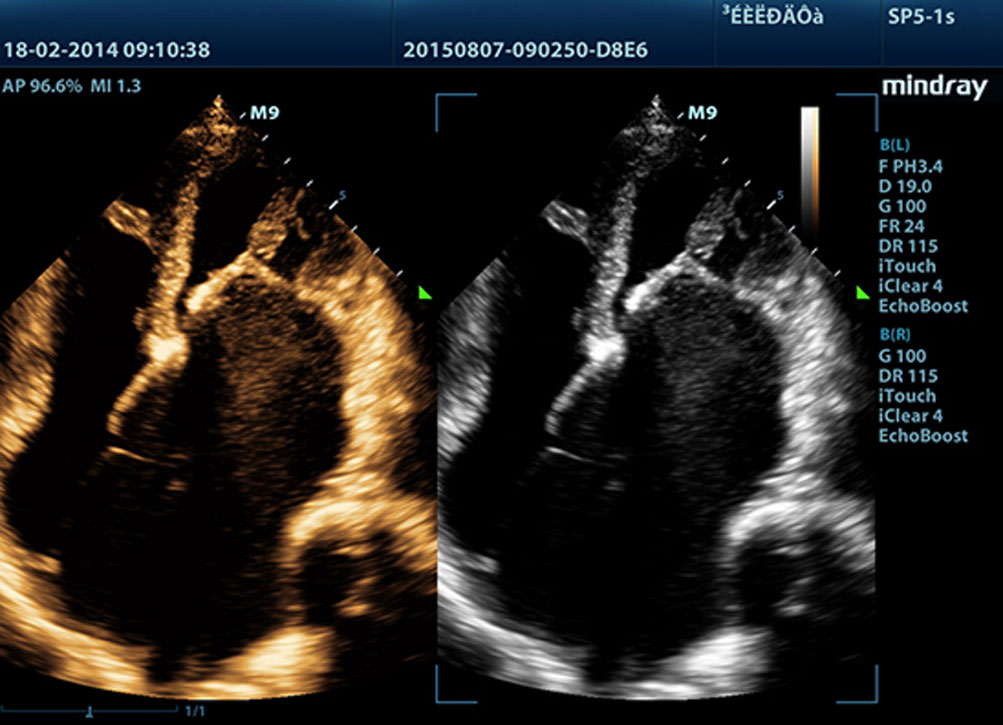

• Echo Boost™

Уникальная адаптивная технология обработки сигнала от Mindray с интеллектуальной системой эходетекции, позволяющая использовать нативную информацию «сигнал/шум» для усиления слабого эхосигнала при одновременном снижении помех. Данная технология обеспечивает оптимизацию яркости изображения и повышение качества визуализации границ и структур сердца.

• Тканевая гармоника (ТГ)

Используя дополнительные гармоники, генерируемые в тканях пограничных слоев, ТГ значительно увеличивает контрастное разрешение и улучшает качество изображения, особенно когда доступ к исследуемому участку затруднен.

• iClear™

Улучшение качества изображения за счет автоматического определения характера ткани.

- Более четкие и непрерывные края

- Плавное и единообразное отображение тканей

- Снижение зернистости в областях без эхосигналов

• Технология датчиков 3T на основе монокристаллов

Все датчики, совместимые с ультразвуковой системой M9, изготовлены по уникальной технологии 3Т, разработанной компанией Mindray, и обеспечивают более четкую визуализацию. Благодаря дополнительному использованию монокристаллических элементов, система M9 отличается более высокой проникающей способностью и улучшенной динамикой цветопередачи, что особенно актуально при сканировании так называемых «сложных» участков.

Ультразвуковая диагностическая система М9 сочетает в себе оптимальную функциональность премиум-класса и мобильность. Основываясь на ультразвуковой платформе нового поколения mQuadro от компании Mindray, портативная система выводит отраслевые стандарты на новый уровень. Модернизированные процессоры приема и передачи сигналов обеспечивают высокую чувствительность и точность обнаружения эхо-сигналов. Благодаря инновационным технологиям, использованным при производстве датчиков, достигается более высокая проникающая способность и улучшается пространственное разрешение, что позволит вам осуществлять высококачественную диагностику.